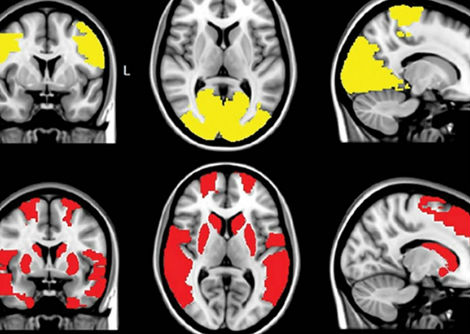

اكتشاف الروابط الدماغية المفقودة التي قد تكون وراء التسبب بالهلوسة عند مصابي مرض باركنسون

رسم خريطة لشبكة الوضع الافتراضي في الدماغ البشري: دراسة تشريحية تشير إلى أن لها تأثيرًا واسع النطاق